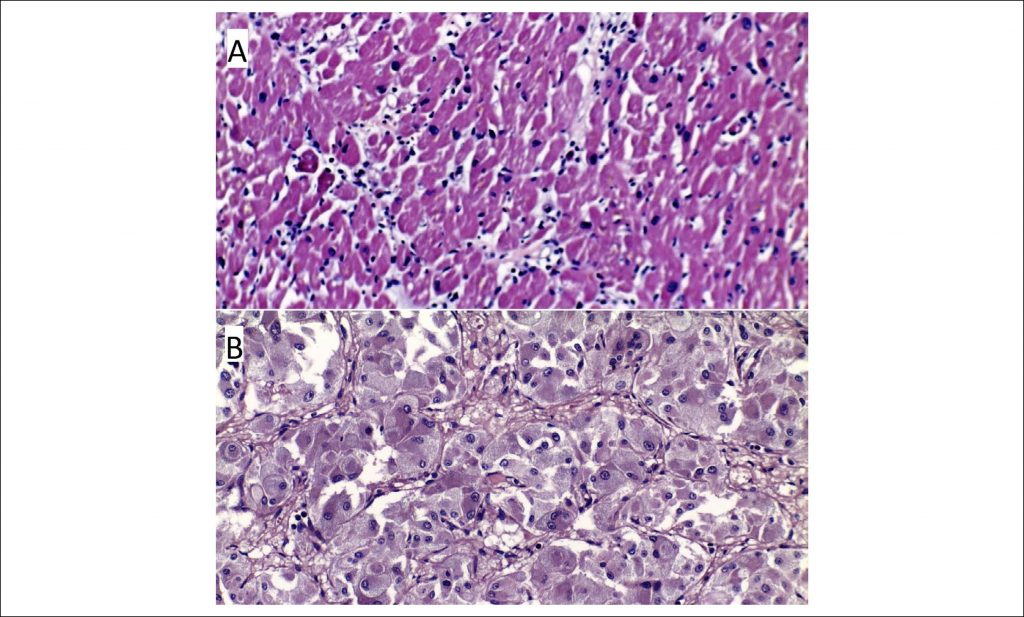

A 64-year-old woman with a history of Diabetes and Hypertension was admitted to the emergency department with acute dyspnea and chest pain. Physical examination revealed hypertension, sinus tachycardia (150 bpm), acute pulmonary edema and poor extremity perfusion. In the context of respiratory failure and hemodynamic instability, she required invasive mechanical ventilation. Blood works showed increased levels of hs-TroponinT (rising from 800 to 1600 ng/L) and the ECG showed poor R wave progression and incomplete right bundle branch block. The echocardiogram revealed a hypertrophied left ventricle, with severe systolic dysfunction and akinetic apical and middle segments. Considering the possibility of acute coronary syndrome, the patient was referred for emergent coronary angiography, which revealed normal coronary arteries. She was admitted to the intensive care unit with the presumed diagnosis of Takotsubo cardiomyopathy. Through the rest of the day, she presented with fluctuating blood pressure and required elevated levels of positive end-expiratory pressure due to pulmonary edema. Despite an apparent favorable evolution, she suddenly developed asystole, refractory to resuscitation efforts, dying less than 24 hours after admission.